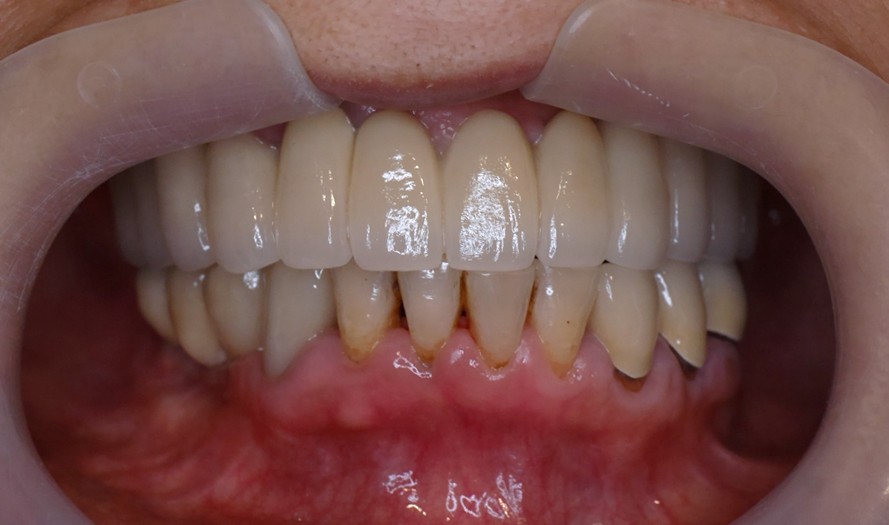

日出全植牙

上顎長期缺牙

上顎長期缺牙,只剩幾個殘存牙根

假牙完成